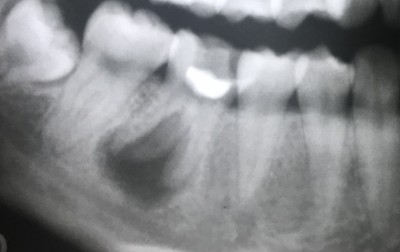

【下顎大臼歯根管治療】

2023.06.16 症例紹介